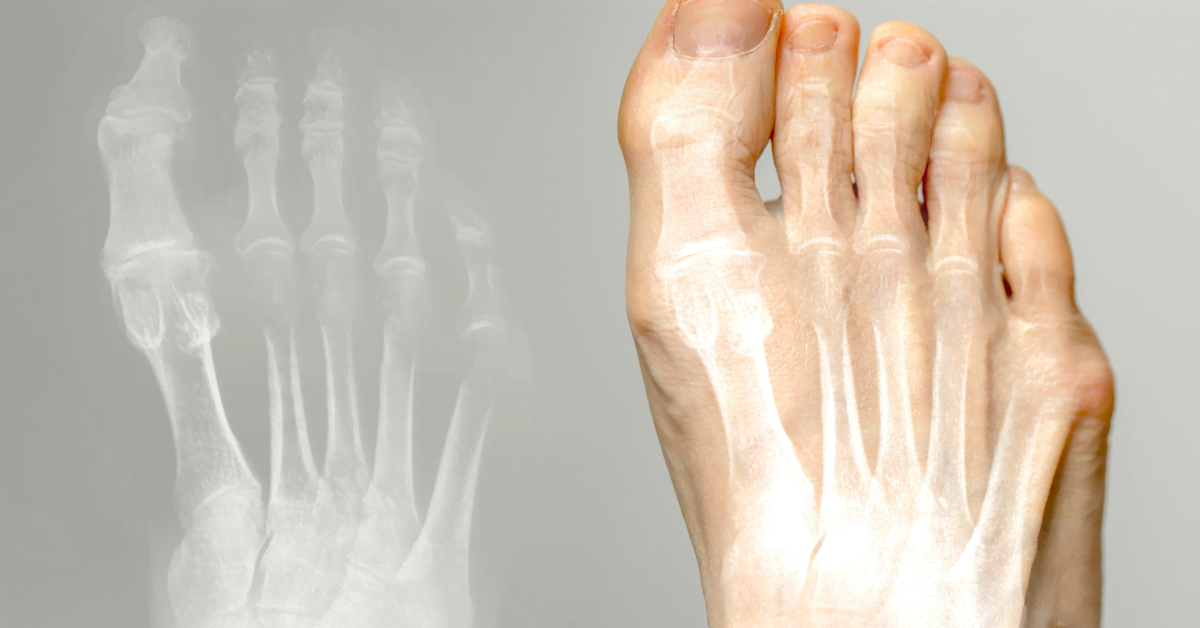

Hallux valgus (Ballenzeh) ist eine Erkrankung, bei der die Großzehe nach innen zeigt und eine Beule an der Basis bildet. Es kann Schmerzen und Unbehagen verursachen. Hier erfahren Sie Ursachen, Behandlung und Vorbeugung.

Die Großzehe biegt sich zu den anderen Zehen hin, wodurch eine Fußbeule entsteht. Ursachen: enge Schuhe, hohe Absätze, Vererbung, Plattfüße oder Arthritis. Schlechte Schuhe verursachen Druck und Reibung, was zu Schleimbeutelentzündungen führen kann.

Beule an der Basis der Großzehe, Schmerzen beim Tragen von Schuhen, Rötung und Schwellung. Brennendes Gefühl, Schwierigkeiten beim Gehen. Manchmal Arthrose in der Großzehe.